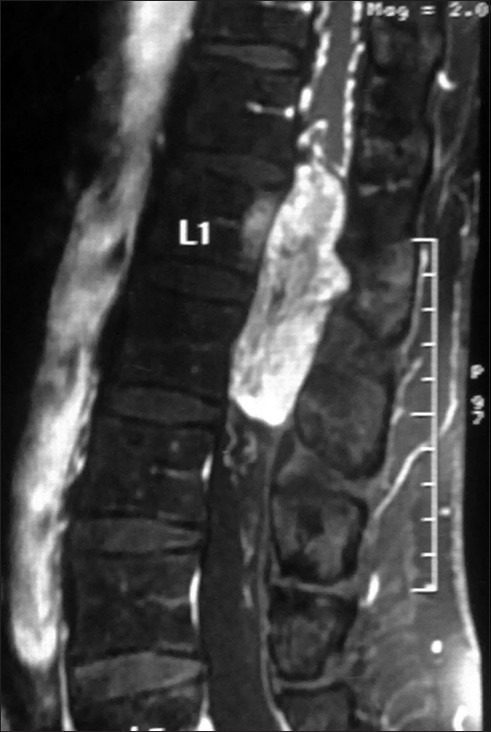

脊髓空洞综合征(Conus-cauda syndrome)是由于脊髓下端和神经根束受累所致。常见的病因是外伤、椎管狭窄、脊髓肿瘤、炎症和感染性疾病,但副神经节瘤是一种罕见病因。这些肿瘤很少具有分泌儿茶酚胺的功能。据我们所知,迄今为止只有五例功能性脊髓副神经节瘤的病例报告。我们报告了一名 50 岁的男性高血压患者,其病变呈分叶状,从 D12 下缘延伸至 L2,术前影像学检查报告为上皮瘤。该病变在术后被证实为功能性副神经节瘤,而患者因该病变引起的严重并发症而死亡,因此凸显了术前诊断和处理的重要性。总之,锥尾功能性副神经节瘤非常罕见。从内科和外科治疗的角度来看,在术前对其进行诊断至关重要。在手术过程中,应非常小心地处理这些肿瘤,以避免儿茶酚胺进入血液。这些肿瘤在围手术期需要麻醉师和内分泌专家的协助。

Conus-cauda syndrome is caused due to involvement of the lower end of the spinal cord and arising bunch of nerve roots. It is caused commonly due to traumatic injury, spinal stenosis, spinal tumors, inflammatory, and infectious conditions, but paraganglioma is a rare cause. These tumors are rarely functional and secrete catecholamine. Till now only five case reports of functional spinal paragangliomas are available to the best of our knowledge. We report a 50-year-old hypertensive male patient with a lobulated lesion extending from lower border of D12 to L2, which was reported as ependymoma on imaging studies done preoperatively. This lesion was confirmed to be a functional paraganglioma postoperatively after the patient died because of its furious complication, thus highlighting the importance of its preoperative diagnosis and management. In conclusion conus-cauda functional paragangliomas are very rare entity. Diagnosing them in preoperative condition is critical from the therapeutic point of view, both medical and surgical. During surgery these tumors should be handled very gently to avoid spillage of catecholamines into blood. These tumors require assistance of expert anesthetist and endocrinologist in the perioperative period.